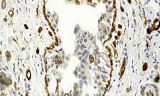

Tissue sections are thin slices of biological tissue prepared for microscopic examination and molecular analysis, fundamental in histopathology, molecular biology, and biomedical research. These sections enable detailed visualization and localization of cellular structures, DNA, RNA, and protein markers, facilitating the study of normal and diseased tissues.

- Localization and identification of mRNA and protein markers within specific tissue contexts.

- Detection of tumor markers and disease-specific genes for diagnostics and research.

- Study of gene and protein expression patterns in normal and pathological tissues.